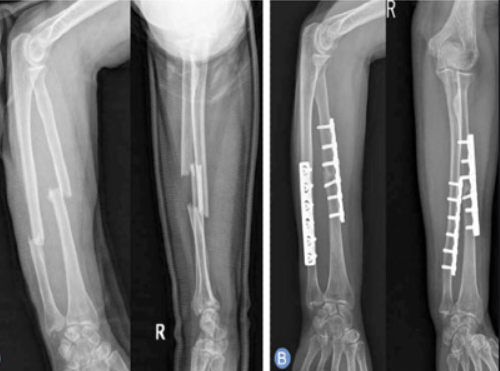

Trauma and Fracture Care

Orthopedic trauma surgeons are trained to quickly assess, stabilize, and treat injuries resulting from accidents, falls, or sports-related trauma.